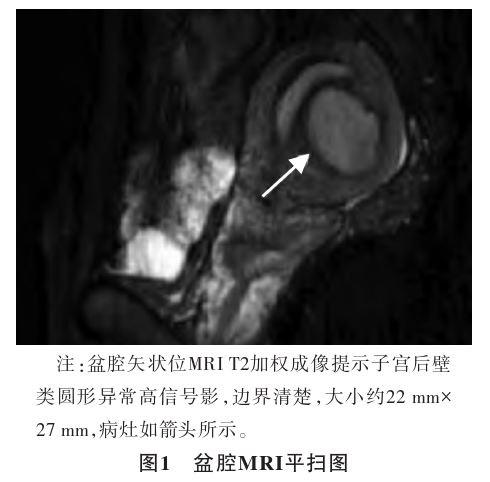

、生化检查、术前感染八项和凝血功能未见明显异常。盆腔MRI平扫示:子宫后壁见类圆形异常信号影,大小约22 mm×27 mm(见图1),考虑子宫肌瘤并出血;子宫内膜异位症

。入院初步诊断:子宫肌壁间子宫内膜异位囊肿。排除手术禁忌证,患者于2024年11月12日在全身麻醉下行宫腔镜

;④囊腔可见子宫内膜腺体及间质;⑤囊腔内为巧克力样液体;⑥囊腔无子宫腺肌病病灶,但囊腔周围的子宫肌层可见子宫腺肌病病灶。本例患者慢性下腹部疼痛3个月余,经腹超声见子宫后壁肌壁间囊实性混合性团块,考虑子宫肌瘤并囊性变。盆腔MRI示子宫后壁见类圆形异常信号影,考虑子宫肌瘤并出血。术中囊腔内有巧克力样积液流出,术后病理可见部分增生期子宫内膜,局部平滑肌增长,其内可见少量子宫内膜腺体排列。结合患者临床表现、影像学检查及术后病理,该患者符合子宫囊性腺肌病的诊断标准。子宫囊性腺肌病通常需与以下疾病相鉴别。

①子宫肌瘤囊性变:子宫肌瘤囊性变时边界清晰,囊腔形态不规则且内壁光滑,无子宫内膜衬覆;子宫囊性腺肌病边界模糊,囊壁有子宫内膜样组织,周围肌层回声粗糙[7-8]。②先天性子宫囊肿:多发生在子宫后壁或者子宫底部,为胚胎发育6周以后,米勒管(副中肾管)在中肾管的外侧形成,此后前者发育为女性生殖道,后者逐渐退化,在这个过程中残留的组织可以形成囊肿,临床无痛经等症状,超声表现为子宫肌层内边界清楚、形态较规则的无回声区[9]。③残角子宫及子宫附腔(accessory cavitateduterine malformation,ACUM):残角子宫有独立的宫腔和内膜,可能与主子宫相通;ACUM为先天畸形,通常位于圆韧带附着点附近,有完整内膜衬覆和肌壁结构;子宫囊性腺肌病则无规律解剖位置,肌层结构不完整[3]。影像学检查对鉴别疾病有重要意义,MRI是首选方式,能清楚地显示盆腔解剖结构、肿块及出血,亦能显示子宫肌层和子宫内膜的界限。因此,术前详细的问诊和全面的影像学检查对明确诊断至关重要。